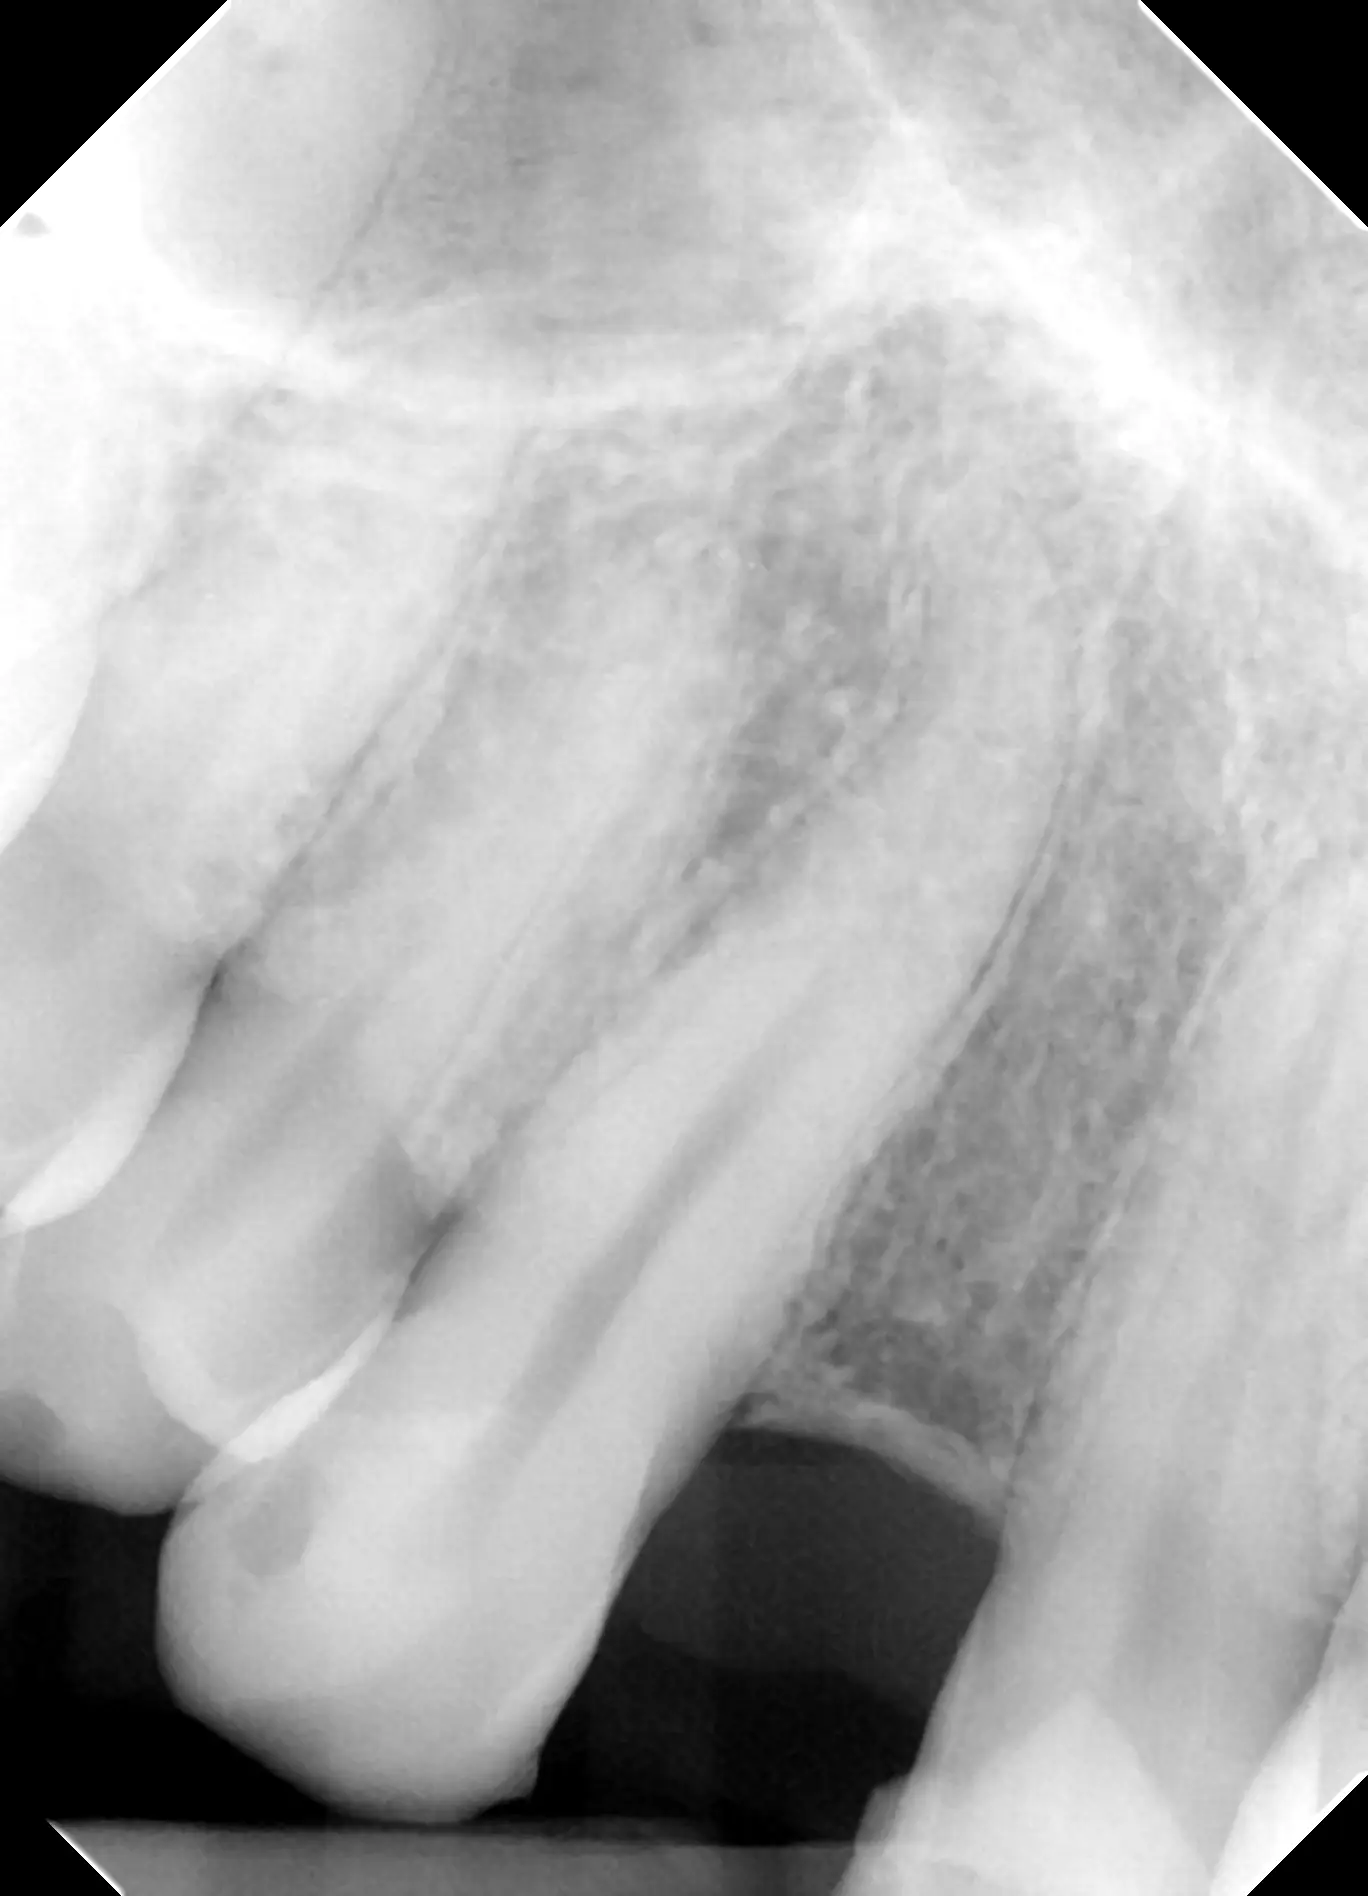

An x-ray taken three years later shows the healthy implant has integrated well with the bone around it. The implant looks stronger than ever and our patient is happy with the results.